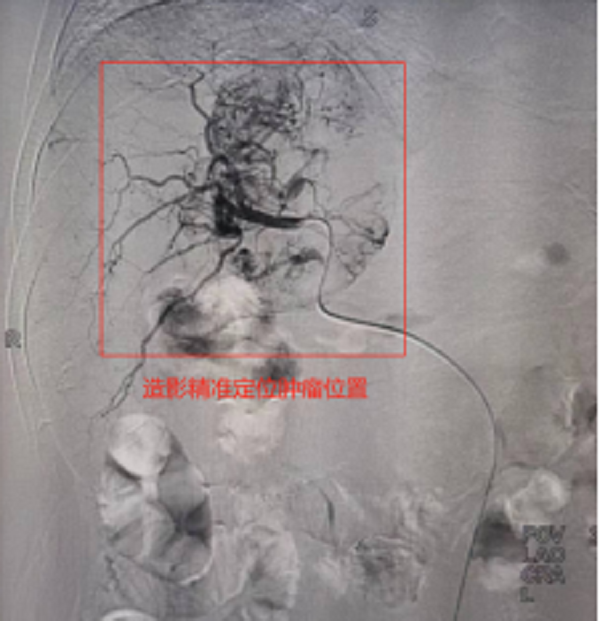

此次来院检查腹部增强CT提示:肝右叶占位性病变,考虑为原发性巨块肝癌,肿瘤大小达到60mmx84mm。患者之前已进行过结肠癌根治性右半结肠切除+胆囊切除术,病情复杂,身体虚弱,患者及家属强烈要求行微创介入治疗。经术前充分沟通及告知各种治疗方案的优缺点后,介入团队选择为患者行TACE介入微创治疗,后续将与靶向、免疫联合治疗达到肝癌的综合治疗。经过积极术前准备,普外科介入团队成功为患者实施了首例肝动脉化疗栓塞术,手术过程顺利,术后患者恢复良好,正在医院接受后续治疗。

肝动脉化疗栓塞术-TACE治疗是经皮穿刺动脉血管,用导管选择肝肿瘤靶血管后,经导管灌注化疗药,再用栓塞物质阻断肝肿瘤血供的治疗方法,是一种把肿瘤细胞“饿死”的介入治疗技术。

TACE治疗全程在影像设备的引导和监视下进行,通过微小的创口能够准确地直接到达病变局部,因此具有微创、精准、安全、高效的优点。